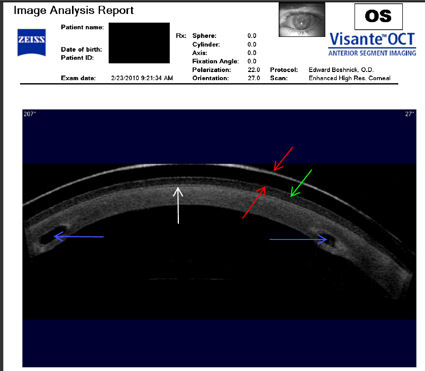

Следующие изображения были получены с использованием метода, называемого оптической когерентной томографией, или ОКТ. Прибор позволяет получить изображение в поперечном сечении путем сканирования передней части глаза (переднего сегмента) лучом света. Думайте об этом как об ультразвуке, использующем свет вместо звуковых волн для создания изображения живых тканей.

У пациентки, описанной ниже, развилась эктазия роговицы после операции LASIK, и ее лечили с помощью ПОТРЕБЛЯЕМЫЕ ВЕЩЕСТВА . Противоположные красные стрелки указывают на переднюю и заднюю поверхности склеральной линзы, которую носит пациент. Зеленая стрелка указывает на заполненное жидкостью пространство между линзой и роговицей. Белая стрелка указывает на заднюю поверхность лоскута LASIK, который никогда не заживает. Синие стрелки указывают на два INTAC, которые имплантированы в роговицу. Тот факт, что пациент сейчас носит склеральные линзы, указывает на то, что имплантация INTAC не привела к восстановлению функционального зрения. Нажмите на изображение, чтобы увеличить.

Изображения любезно предоставлены доктором Эдвардом Бошником, который посвятил свою практику восстановлению качественного зрения и информации о эктазия после операции LASIK .